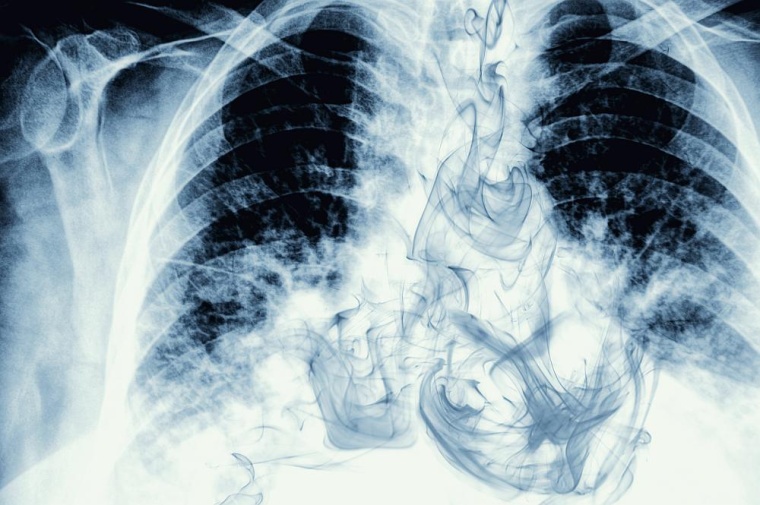

Lungenkrebs ist eine tückische Erkrankung, die wegen ihrer oft unspezifischen Symptome häufig erst spät erkannt wird. Eine erfolgreiche Behandlung wird daher meist erschwert oder sogar verhindert.

Abhilfe könnte hier ein Programm zur Früherkennung von Lungenkrebs schaffen, das aktuell diskutiert wird. Das Programm würde sich an die besonders gefährdete Gruppe langjähriger Raucherinnen und Raucher richten und mithilfe der Niedrigdosis-Computertomografie durchgeführt werden.

Bei vielen Krebserkrankungen ist die frühe Diagnose für eine erfolgreiche Behandlung entscheidend, und gerade bei Lungenkrebs ist dies Studien zufolge der Fall. Daher wird aktuell im Gesundheitswesen eine Früherkennung von Lungenkrebs mithilfe der Niedrigdosis-Computertomografie vorbereitet. Mit einem solchen Programm zur Lungenkrebsfrüherkennung soll die Prognose von Patientinnen und Patienten verbessert werden, weil die Erkrankung in frühen, besser behandelbaren Stadien erkannt werden kann.